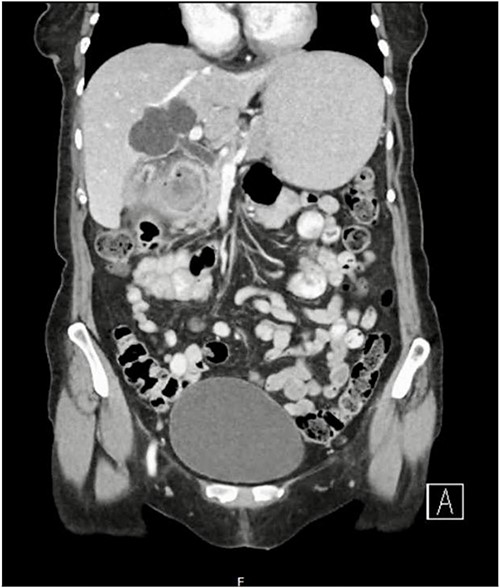

A 79-year-old female presented with a 5-day history of nausea, vomiting, and abdominal discomfort but no overt pain. She was hemodynamically stable. On examination, she had mild right upper quadrant tenderness but no signs of peritonism and a negative Murphy’s sign. Computed tomography (CT) of the abdomen and pelvis revealed features suggestive of acute cholecystitis, complicated by cholecystoduodenal fistula with a large (3.5 cm) gallstone impacted at the second part of the duodenum (Figs 1 and 2), consistent with Bouveret syndrome. The patient was kept fasting and a nasogastric tube was inserted for gastric decompression. She underwent a gastroscopy in an attempt to remove the impacted gallstone. However, the stone could not be retrieved due to its severe impaction, most evident on the pylorus side of the duodenum (Fig. 3).

Coronal CT image of abdomen demonstrating fistulous connection between the gallbladder and duodenum and a large gallstone.